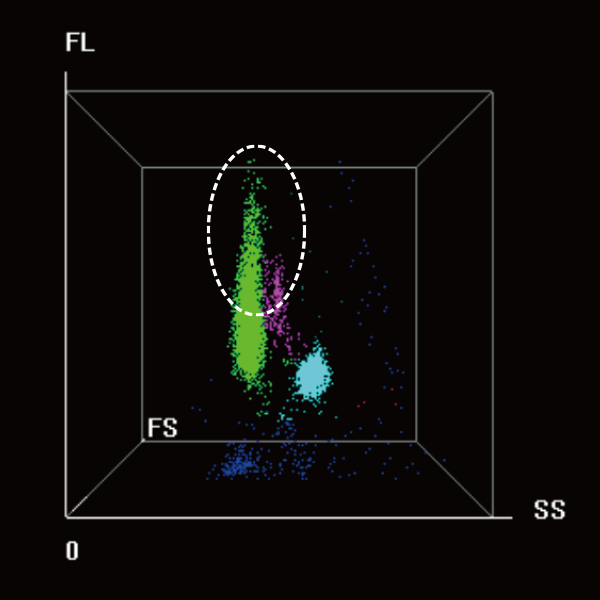

Higher Specificity for Hematological Malignant Cells

By using the HMC scattergram and combining information from the DIFF and WNB scattergrams, precise alarms for blast cells, abnormal lymphocytes, and abnormal promyelocytes are achieved, effectively aiding clinical diagnosis.

The specificity has been improved by approximately 40% compared to CD mode.

Abnormal promyelocyte

Blast

Abnormal lymphocyte

Typical samples of

acute promyelocytic

leukemia (APL)

Blasts

Abn. promyelocyte?

Typical samples of

acute monocytic leukemia (M5)

Blasts

Typical samples of

hairy cell leukemia

Abn. Lymph?

Blasts

HMC 3D scattergram